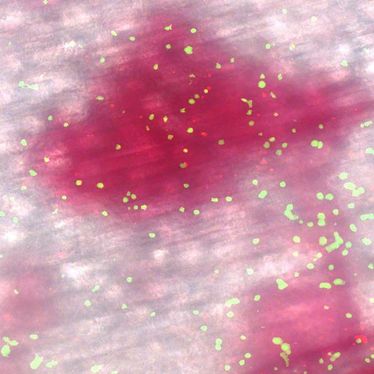

Münster (CIM) - Blutplättchen sind für die Blutgerinnung und den Wundverschluss verantwortlich. Sind zu wenige davon im Blutgewebe, kann das aber auch zu fatalen Blutungen führen – warum, war bisher unklar. Den Grund haben nun Wissenschaftler aus dem Exzellenzcluster Cells in Motion (CiM) der Universität Münster herausgefunden und in einer aktuellen Publikation in The Journal of Experimental Medicine beschrieben.

Für die Forscher um Dr. Carina Hillgruber, wissenschaftliche Mitarbeiterin der Medizinischen Fakultät, und Prof. Dr. Tobias Görge, CiM-Gruppenleiter und Oberarzt der Klinik für Hautkrankheiten am Universitätsklinikum Münster, sind die „Schuldigen“ klar: Weiße Blutzellen (Leukozyten), die während der Entzündungsreaktion die Blutbahn verlassen, lösen in der Abwesenheit von Plättchen (Thrombozyten) Blutungen aus. Problematisch sind solche Blutungen, wenn es zum Beispiel bei einer Transplantation oder während einer Chemotherapie zu Komplikationen mit Plättchenverlusten kommt.

Für die Forscher um Dr. Carina Hillgruber, wissenschaftliche Mitarbeiterin der Medizinischen Fakultät, und Prof. Dr. Tobias Görge, CiM-Gruppenleiter und Oberarzt der Klinik für Hautkrankheiten am Universitätsklinikum Münster, sind die „Schuldigen“ klar: Weiße Blutzellen (Leukozyten), die während der Entzündungsreaktion die Blutbahn verlassen, lösen in der Abwesenheit von Plättchen (Thrombozyten) Blutungen aus. Problematisch sind solche Blutungen, wenn es zum Beispiel bei einer Transplantation oder während einer Chemotherapie zu Komplikationen mit Plättchenverlusten kommt.